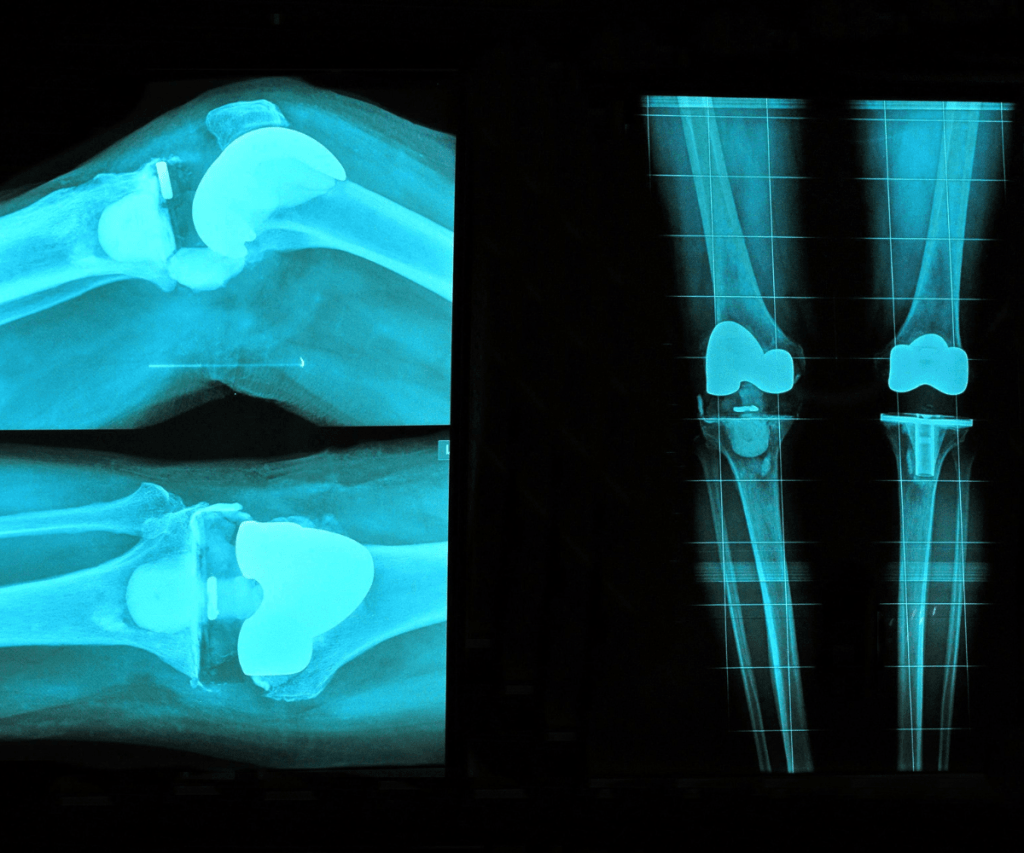

Operativni poseg na prizadetem sklepu, pri katerem želimo obnoviti delovanje sklepa z vstavitvijo umetnega sklepa imenujemo ENDOPROTEZA SKLEPA. Vstavitev umetnega kolena je ena izmed najpogostejših operacij na kolenu. Življenjska doba večine vgrajenih endoprotez je vsaj 15 let.

Operacija:

- traja od 60 do 120 minut,

- kirurg odstrani poškodovano kost in vstavi nov umetni sklep, ki zagotovi funkcije kolena,